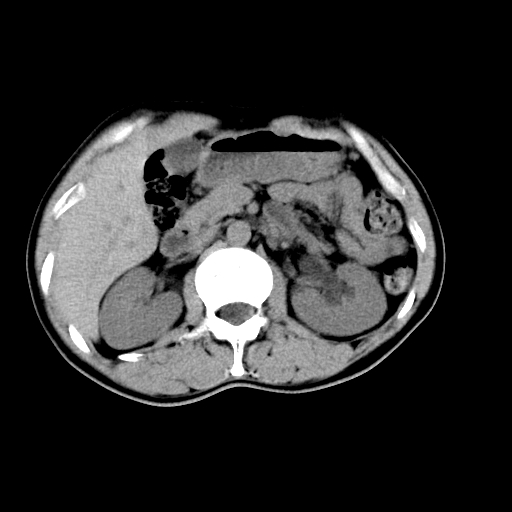

男,47岁,左输尿管结石碎石治疗后10余日。彩超示:左输尿管下段狭窄、输尿管积水。请各位讨论一下左输尿管下段结石还是静脉石?

象是第二狭窄处结石伴以上输尿管、肾盂轻度积水。

输尿管结石伴以上输尿管、肾盂轻度积水。

两侧髂总动脉壁斑状及点状钙化.左侧输尿管行经与左髂总动脉相交后见高密度影,且下段输尿管管腔未见扩张,应该要考虑结石伴以上输尿管及肾盂积水.但右侧结节状高密度影,也应该是结石吧!那以上输尿管未见扩张呢!因此静脉结石可能性也较大.请问楼主碎石前左侧输尿管结石位置.

虽左侧有轻度肾盂积水但不支持结石。1结石边周应该有软组织包绕呈晕征。2钙化点前面见输尿管影也不支持是结石。3彩超没提结石。建议超生复查。

输尿管先位于腹部,后进入盆腔,最后斜穿膀胱壁开口于膀胱,因此,临床上常将输尿管分为腹段、盆段和壁内段。第1个狭窄:在肾盂与输尿管移行处。第2个狭窄:在跨过髂血管处。第3个狭窄:在穿过膀胱壁处。这些狭窄是结石容易滞留的部位。

左侧输尿管有轻度扩张伴有肾盂积水,输尿管下段周围的高密度影不象在输尿管内。